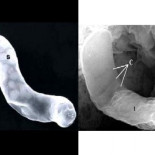

Sistema anticopia para exámenes

Un peculiar sistema para evitar que los alumnos copien en los exámenes